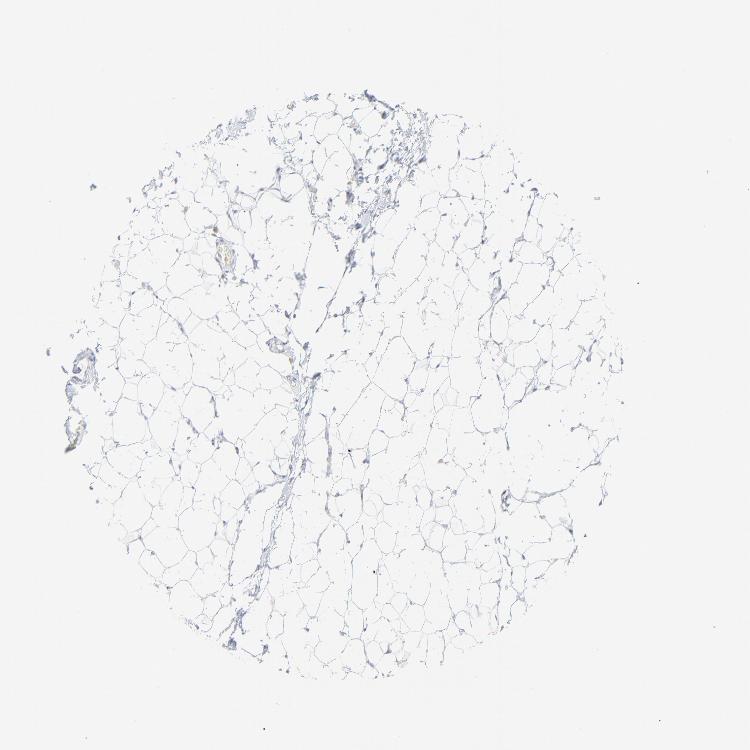

SOFT TISSUE 2 - Antibody stainingi

Antibody staining in the annotated cell types in the current human tissue is reported as not detected, low, medium, or high, based on conventional immunohistochemistry profiling in selected tissues. This score is based on the combination of the staining intensity and fraction of stained cells.

Each image is clickable and will lead to virtual microscopy that enables deeper exploration of all samples and also displays staining intensity scores, fraction scores and subcellular localization as well as patient and tissue information for each sample.

Antibody HPA002695Antibody CAB016549Antibody CAB016550

Fibroblasts Not detectedNot detectedNot detected

Peripheral nerve Not detected--